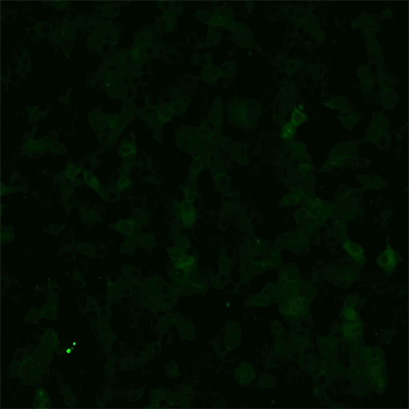

轮状病毒感染的非洲绿猴肾细胞(MA104)的活细胞成像。MA104 细胞,以绿色显示,表达钙指示剂GCaMP6s,其中绿色增加表示细胞内钙增加。在这个活体细胞成像视频中,轮状病毒感染的细胞呈红色——Hyser实验室此前曾报道,在轮状病毒感染期间,轮状病毒会导致受感染细胞中的细胞内钙增加,随后激活邻近细胞中的特定信号通路,从而引起未感染细胞的细胞内钙信号的增加(Chang-Graham et al., 2020)。

轮状病毒感染的非洲绿猴肾细胞(MA104)的活细胞成像。MA104细胞,显示为绿色,表达钙指示剂GCaMP6s,其中绿色增加表示细胞内钙增加。在这个活细胞成像视频中,轮状病毒感染的细胞呈红色——Hyser实验室之前报道过,在轮状病毒感染期间,轮状病毒导致受感染细胞内钙的增加,并随后激活邻近细胞中的特定信号通路,从而引发未受感染细胞的细胞内钙信号的增加(Chang-Graham et al., 2020)